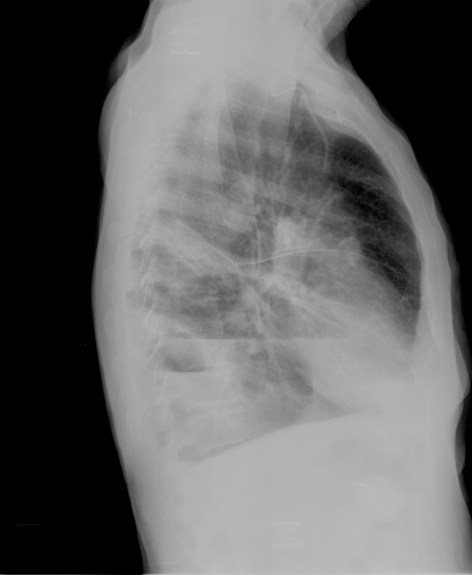

Solución: Es un estudio Normal. Silueta cardiomediastínica y parénquimas pulmonares sin alteraciones significativas.